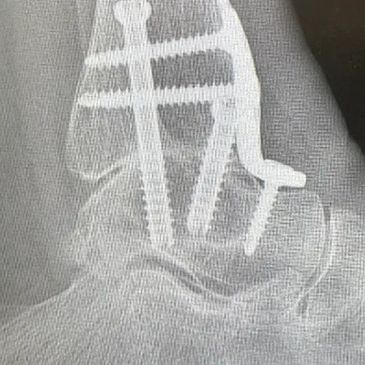

Midfoot fusion surgery is used to treat painful arthritis or instability in the middle of the foot that affects walking and standing. By permanently stabilising the affected joints, it relieves pain and improves everyday function.

A midfoot fracture can cause pain, swelling and difficulty walking. Surgical fixation realigns and stabilises the bones to support healing and restore function.